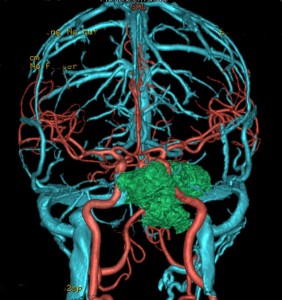

左動眼神経麻痺が急速に進行した例です。斜台から左海綿静脈洞,錐体骨尖を侵す頭蓋底軟骨肉腫です。左内頚動脈は腫瘍に取り囲まれています。

CTでは腫瘍実質部分が増強されます。不規則な骨破壊像・浸食像が特徴的です。